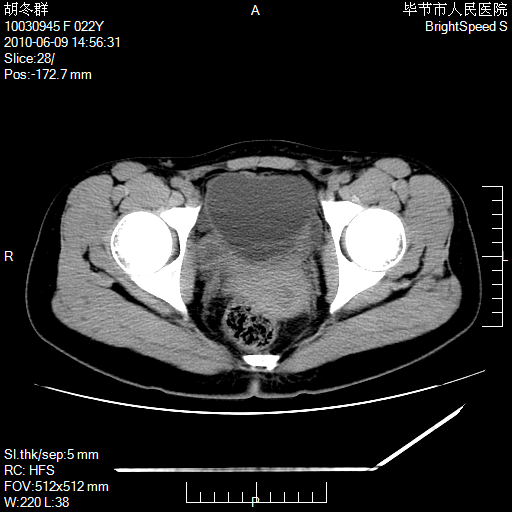

患者23岁,发现腹部包块3月。

我当时考虑重复膀胱,但我错得很厉害,我不明白,囊肿排尿后为什么能到膀胱位置。

囊性病变,可以增强检查,不除外输尿管囊肿

盆腔内囊性占位性病变;考虑左侧卵巢囊腺瘤。

有分隔、壁薄,支持考虑左侧卵巢囊腺瘤。

左侧卵巢浆液性囊腺瘤。

有分隔、壁薄,支持考虑左侧卵巢囊腺瘤。排尿后,膀胱缩小,由于重力作用,肿块下移就到了膀胱位置,很好理解。